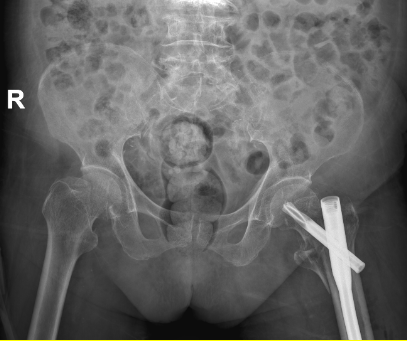

经过充分的术前准备和病情讨论,专家团队一致认为,虽然手术风险极高,但在严格把控手术指征和做好充分应急预案的前提下,为莫婆婆实施闭合复位股骨近端防旋髓内钉(PFNA)内固定术是最佳选择。该术式具有创伤小、出血少、固定牢固、术后恢复快等优势,能最大程度降低手术风险,促进患者早期康复。

征得患者及家属同意后,手术当日,骨科一区医护团队密切配合,在C型臂X线机的精准引导下,仅通过几个微小切口,便顺利完成骨折闭合复位和内固定植入,手术过程顺利,出血量少,手术时间短。术后,莫婆婆生命体征平稳,被安全送回普通病房。

术前与术后